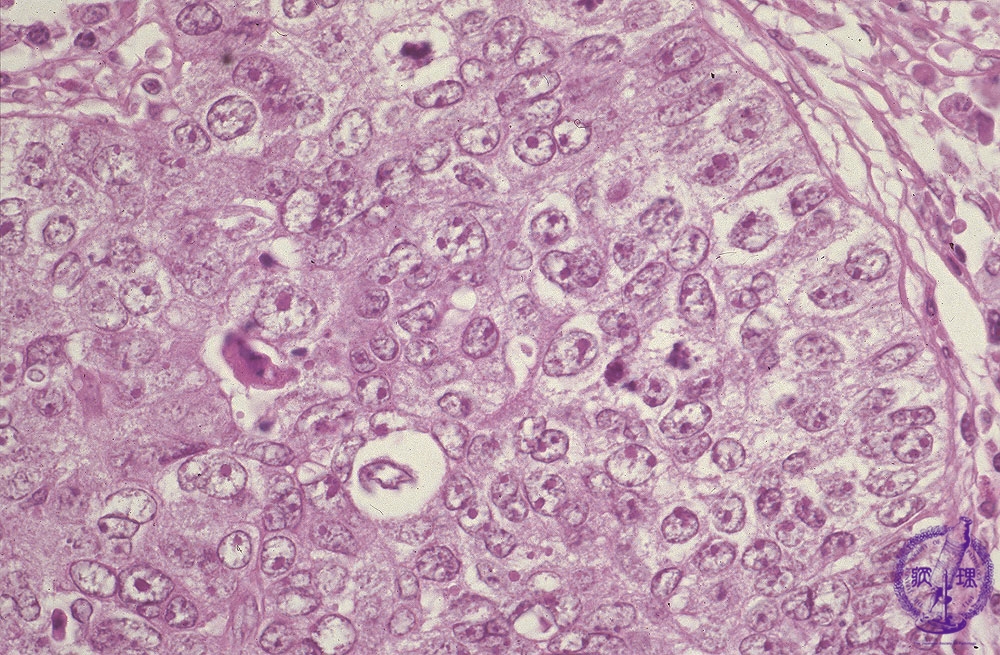

Macroscopic view: Macroscopically, tumor has a lobulated appearance as in thymoma. The tumor circumference is irregular (dotted line), indicating invasion into the surrounding tissue.